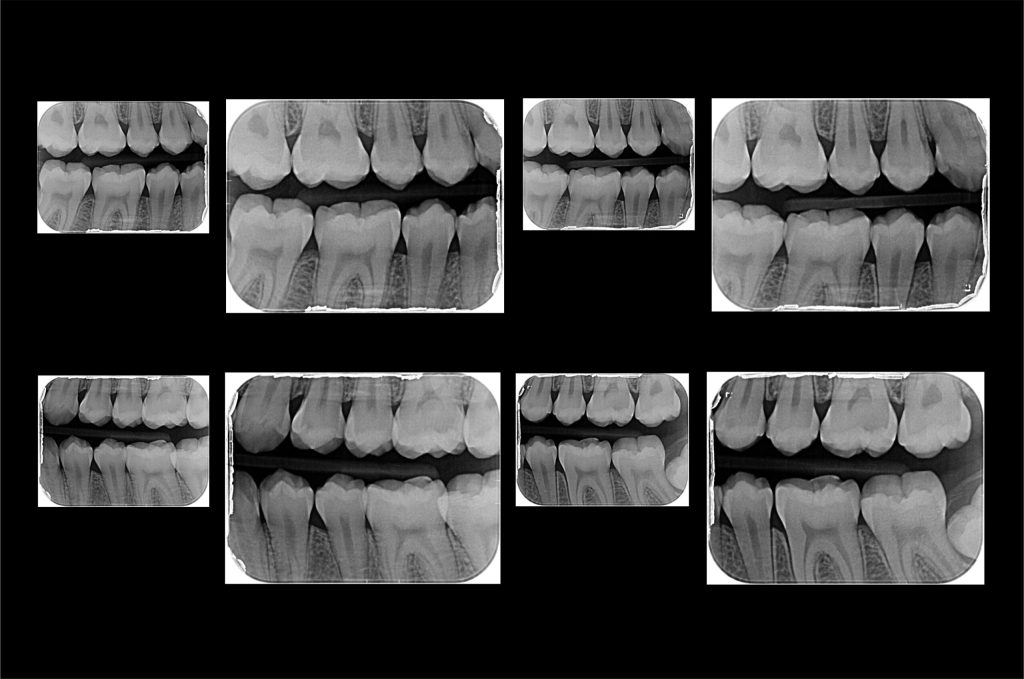

El Centro Radiológico Diagnóstico Oral 3D, es una empresa antioqueña que ofrece a sus pacientes desde el año 2009, tecnología de vanguardia en radiografías tridimensionales con calidad fotográfica. Las posibilidades para mejorar la eficacia en los diagnósticos bucales son evidentes, también lo son las posibilidades de manipulación de imagen. El sistema de imágenes en 3D ofrece detalles sin precedentes, convirtiéndola en la opción idónea para la mayoría de aplicaciones odontológicas, incluyendo implantes, tratamiento de conductos, ortodoncia, odontopediatría, periodoncia y cirugía

Diagnóstico de caries y enfermedades periodontales

Evaluación de patologías dentales y maxilofaciales